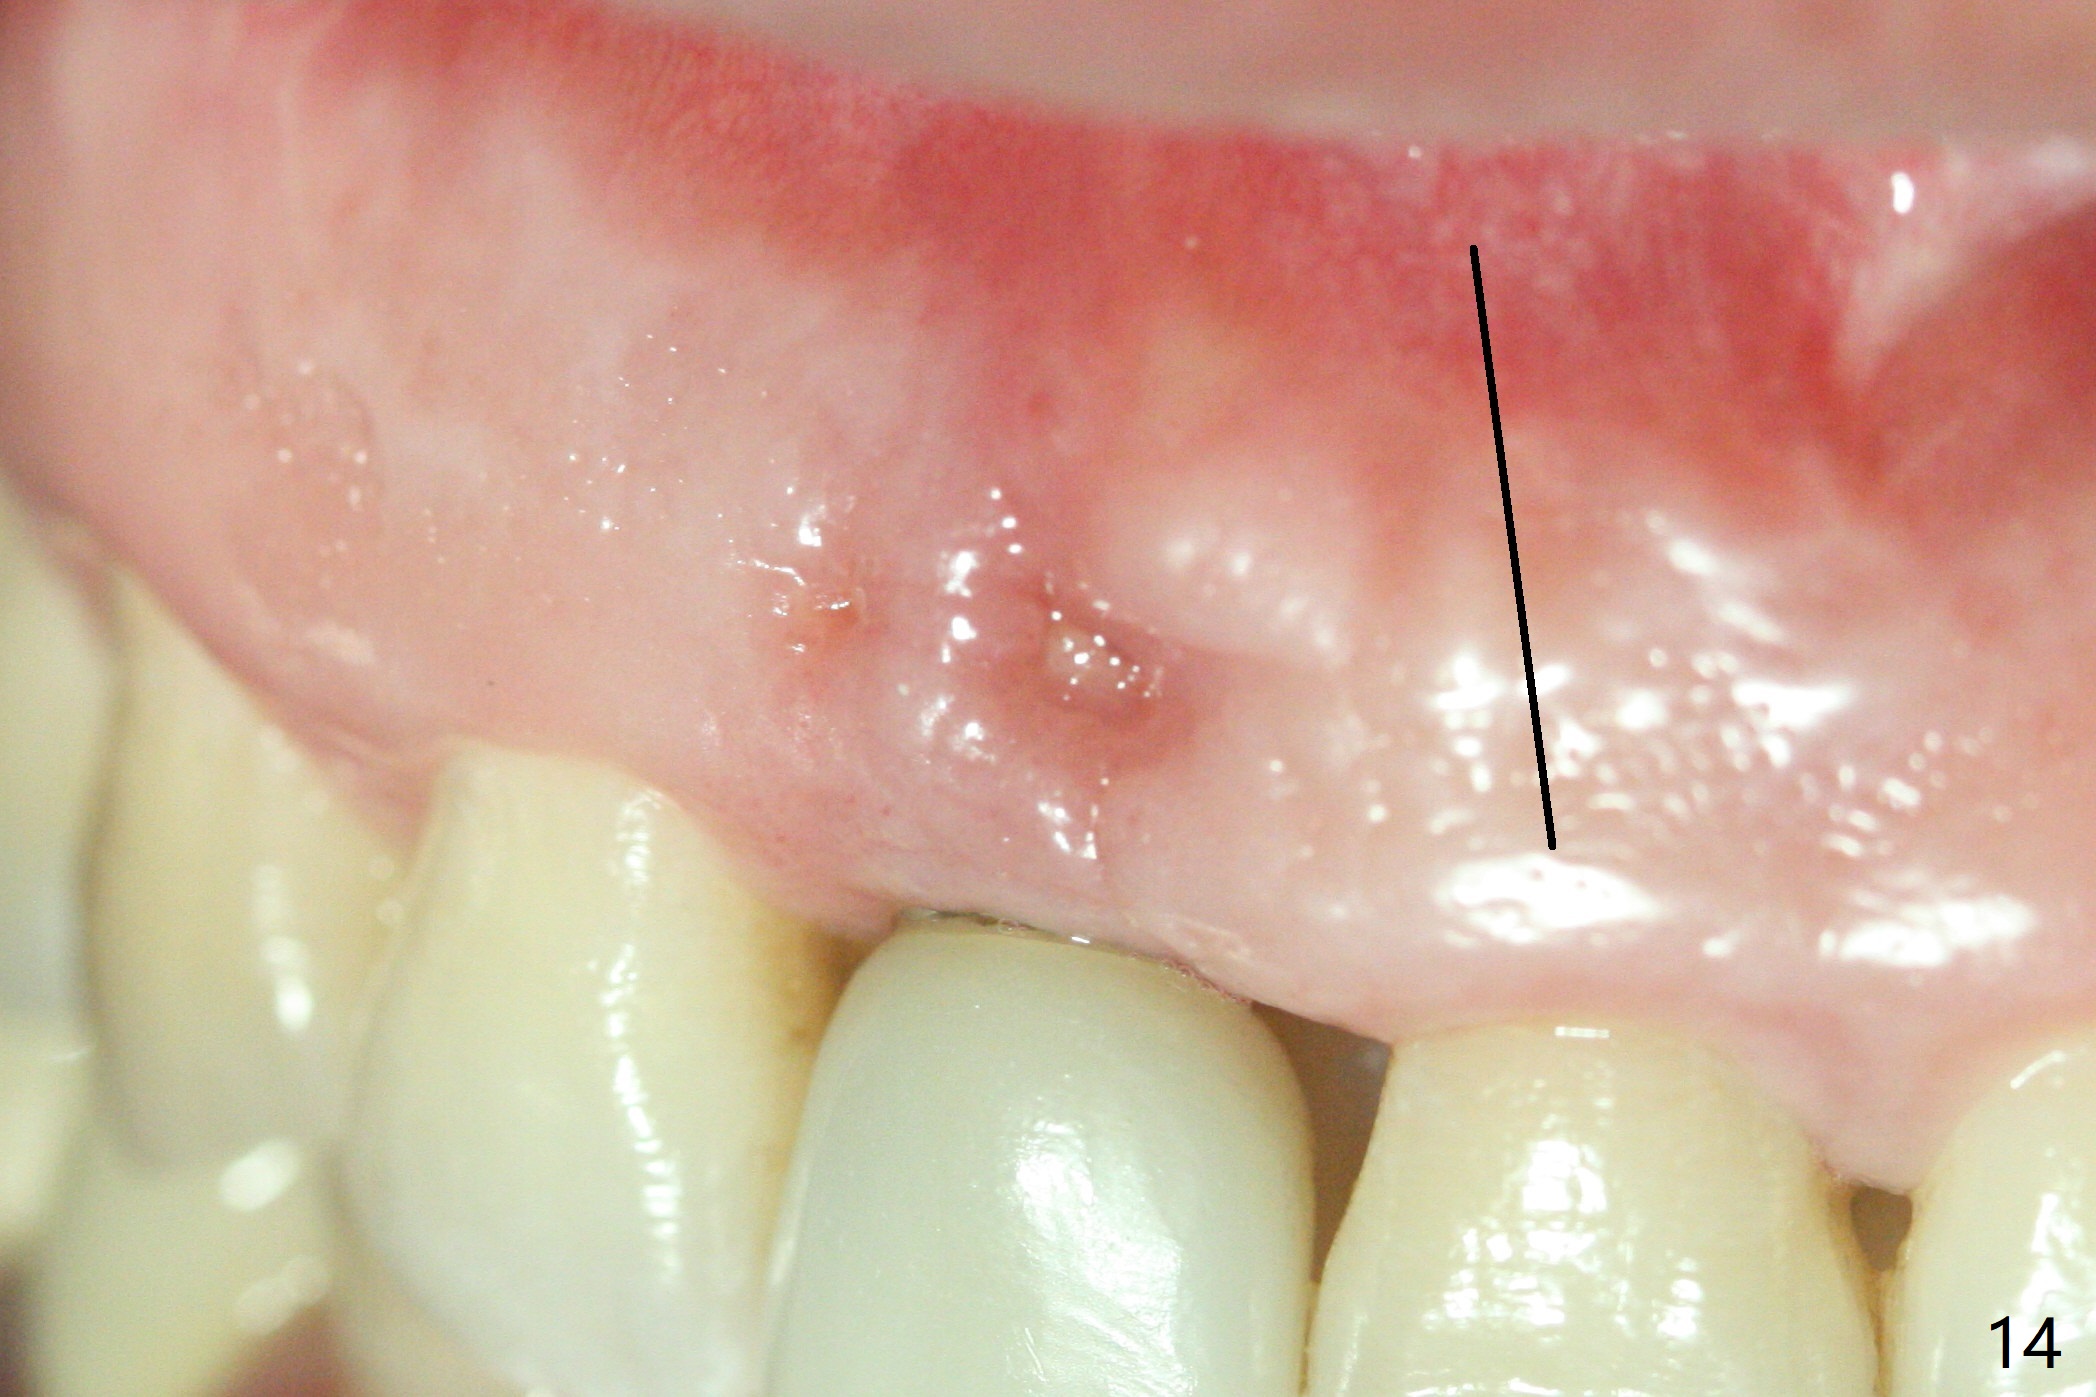

The patient returns because of purulent exudate from the buccal fistula (Fig.1 *) 1 year 9 months postop (1 year 3 months post cementation). Preop CT shows buccal thread exposure (Fig.2 arrowheads). To prevent postop gingival recession, a semilunar incision is made between the fistula and the gingival margin (Fig.3). After removal of granulation tissue (Fig.4), allograft in sticky bone form is packed (Fig.5). Following placement of PRF membrane and 6-month collagen membrane, the wound is closed (Fig.6). Since the implant (Fig.7 I) thread exposure is within bone (B) boundary (Fig.8 red dashed line), bone graft with PRF should be able to take care of periimplantitis (A: abutment). To prevent periimplantitis in similar situation, the immediate implant should be placed deep (not necessarily long, 18 mm) and narrower (3.5 mm instead of 3.8 mm). The defective buccal plate should be repaired with sticky bone and collagen membrane with incision if necessary. The wound does not dehisce 1 week postop (Fig.9) or 3 weeks postop (Fig.10, immediately post suture removal). Although bone graft seems to stay in place 6 months postop (Fig.11,12), the patient complains of bone graft expulsion sometimes. The buccal gingiva has deficiency (Fig.13). To fix it, make a remote incision (Fig.14 black line) and dissect before gingiva graft (Fig.15 dashed line). After removal of crown/abutment, the sinus track and implant surface are treated with Waterlase. A shorter cuff abutment is placed (4.5x5(4 to 3) mm) with a new provisional. The patient feels better with reduced sinus track 2 weeks postop (Fig.16).